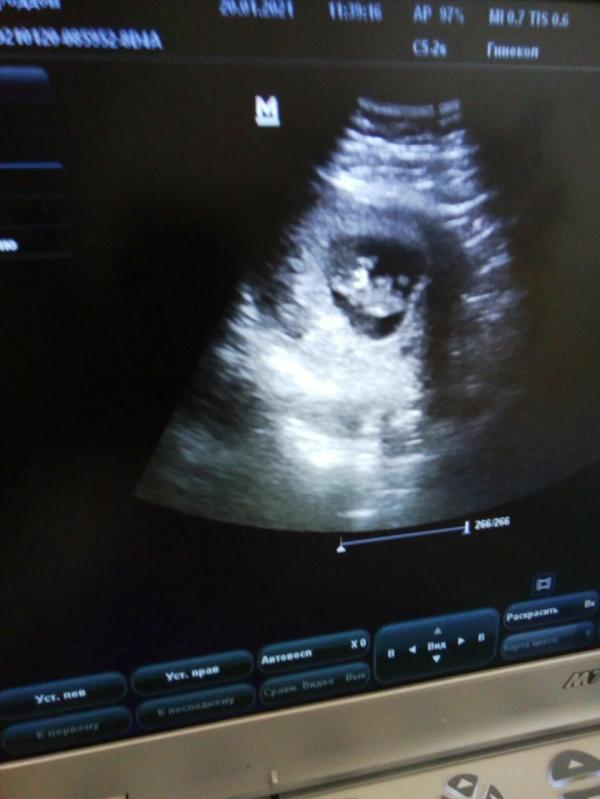

Завтра буду на узи ,и ещё раз спрошу кто))